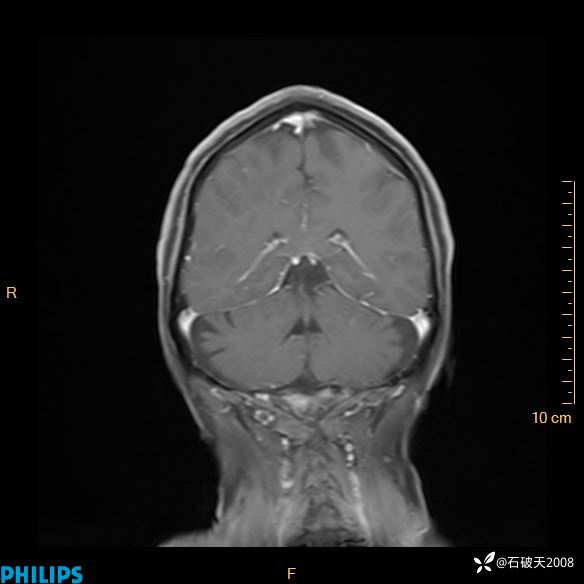

2024.2.21MR

增强冠状位